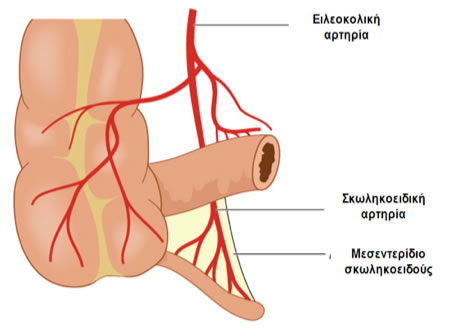

Περιβάλλεται από περιτόναιο, η πτυχή του οποίου σχηματίζει το μεσεντερίδιο της, όπου διαδράμει η σκωληκοειδική αρτηρία, κλάδος της ειλεοκολικής (ειλεοτυφλικής) αρτηρίας.